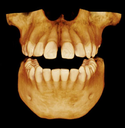

Introducing the CS 9300 Premium Panoramic, Cephalometric, and Cone Beam System from Carestream Dental – your ultimate solution for top-quality dental imaging. This state-of-the-art machine offers both 2D panoramic and cephalometric dental X-rays, as well as adjustable 3D cone beam images in up to seven different field of view sizes, extending up to 17x13.5 cm. This comprehensive range of imaging capabilities makes it a versatile tool, perfect for supporting a wide array of dental, surgical, or orthodontic examinations.

With the CS 9300 Premium, you can expect unparalleled image clarity and precision, allowing you to confidently diagnose and plan treatments with ease. Whether you're performing routine dental check-ups, complex surgical procedures, or orthodontic assessments, this system ensures outstanding results.

The CS 9300's 2D panoramic x-ray imaging capabilities are powered by variable focal trough technology, which provides optimal clarity for every image. The system's 3D imaging capabilities are based on cone beam technology, which delivers high-resolution images with a low radiation dose.

- Orthodontics

- Oral and maxillofacial surgery